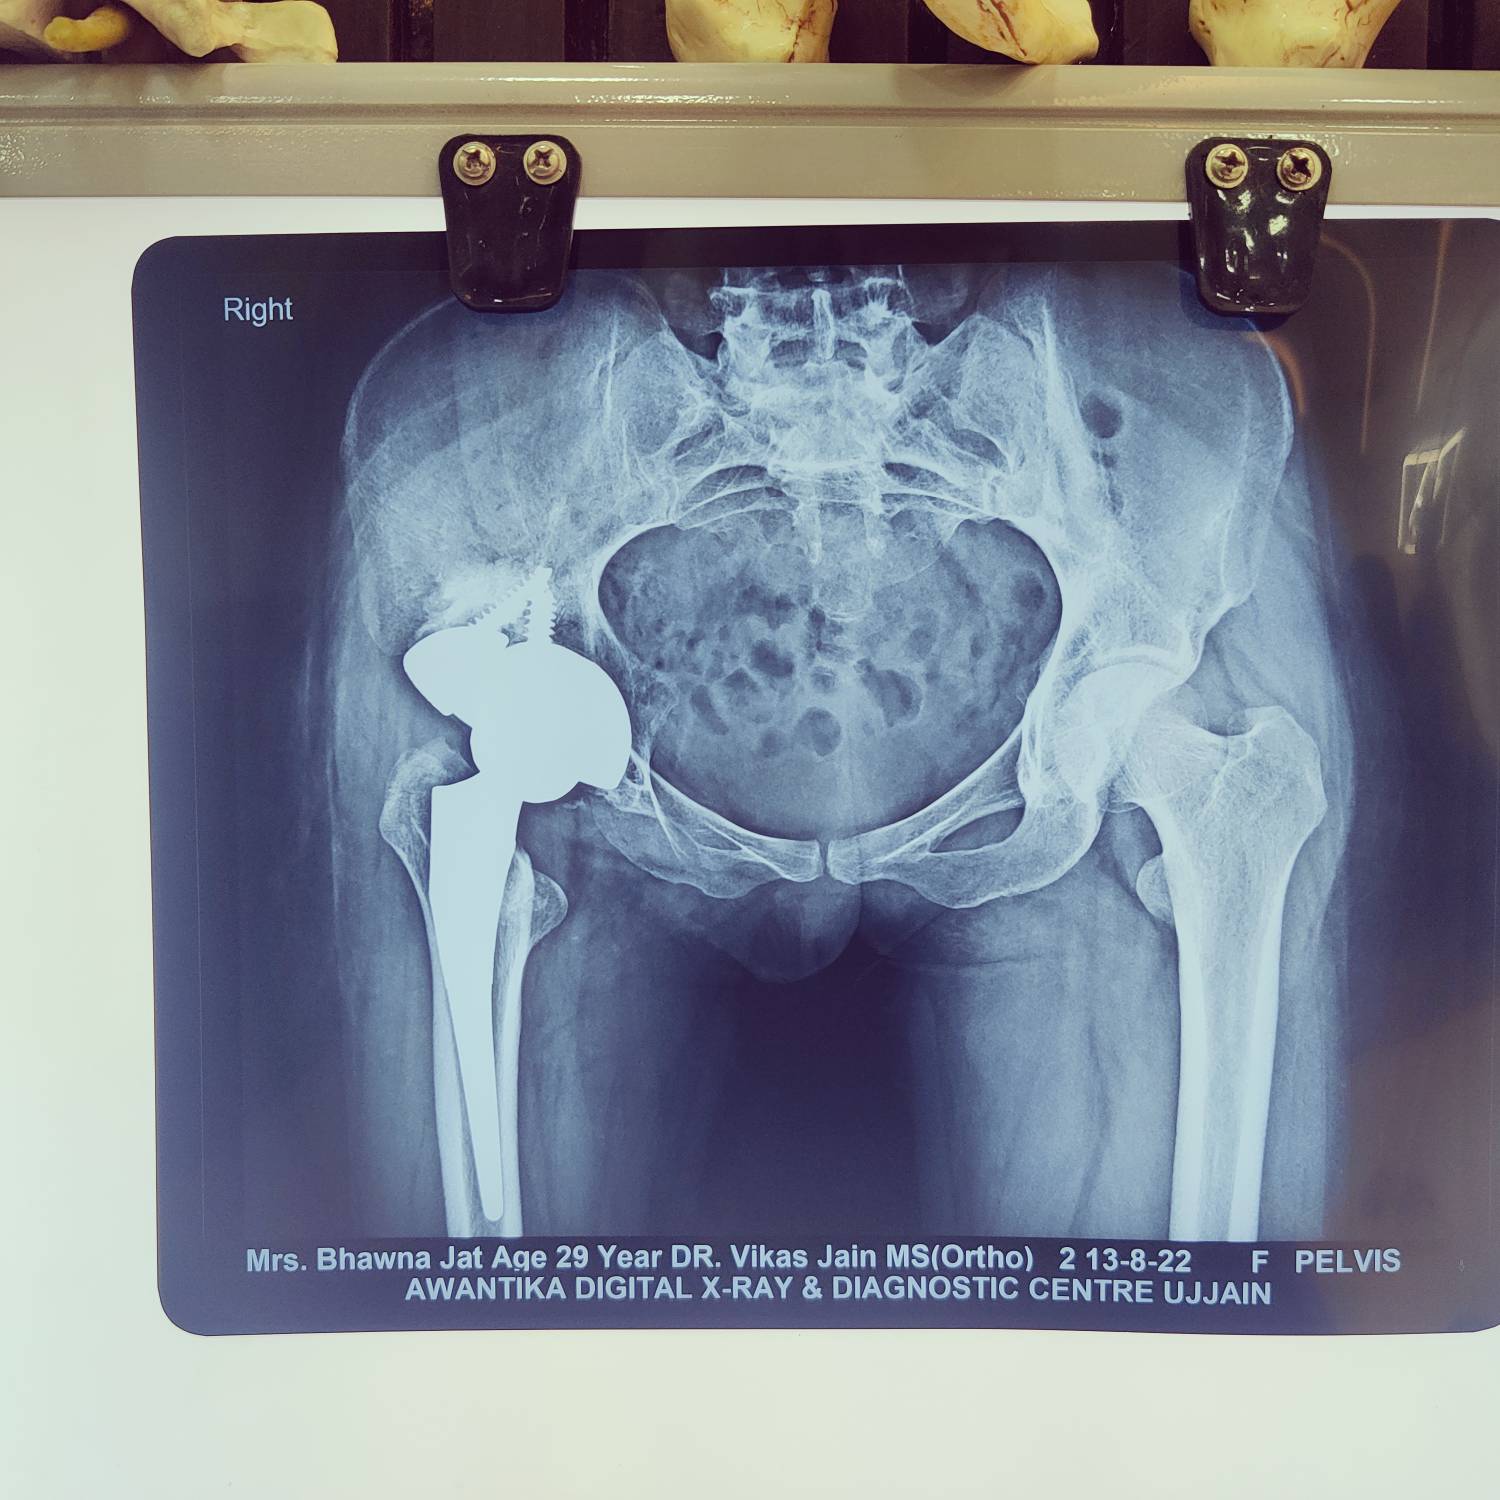

Revision Total Hip Replacement Surgery

INTRODUCTION This means that part or all of your previous hip replacement needs to be revised. This operation varies from very minor adjustments to massive operations replacing significant amounts of bone and hence is difficult to describe in full. Total Hip Replacement (THR) procedure replaces all or part of the hip joint with an artificial device (prosthesis) with a plastic liner in between to restore joint movement Why does a hip need to be revised? Pain is the primary reason for revision. Usually the cause is clear but not always. • Plastic (polyethylene) wear : This is one of the simpler revisions where only the plastic insert is changed. • Dislocation (instability) : means the hip is popping out of place. Repositioning of the implants has to be planned. • Loosening of either the femoral or acetabular component: This usually presents as pain but may be asymptomatic. For this reason, you must have your joint followed up for life as there can be changes on X-ray that indicate that the hip should be revised despite having no symptoms. • Infection usually presents as pain but may present as an acute fever or a general feeling of unwell. Such revisions may be performed in a single or two stages to prevent recurrence of infection. • Osteolysis (bone loss): This can occur due to particles being released into the hip joint that result in bone being destroyed. • Pain from hardware e.g. cables or wires causing irritation. Such procedures are amongst simpler revisions where patients can expect excellent results. PRE-OPERATIVE PHASE • Your surgeon will send you for routine blood tests to rule out infection, CT scan to look closer at the anatomy, and bone scans to help to determine if a component is loose. • X-rays and/or MRI will be considered. • Aspiration of the hip joint is occasionally done to diagnose or rule out infection • Patient will be asked to undertake a general medical check-up with a physician • Patient should have any other medical, surgical or dental problems attended to prior to the surgery in order to prevent a risk of infection. • Cease aspirin or anti-inflammatory medications 10 days prior to surgery as they can cause bleeding. • Any antiplatelet drugs / blood thinners such as clopidogrel, warfarin will be stopped 3-7 days prior to the date of surgery. • Surgical consent will be explained to the patient detailing the procedure as well as the risks involved, if any. • Blood transfusion, if required will be informed and done. Day of surgery • You will meet the nurses and answer some questions for the hospital records • You will meet your anesthetist, who will ask you a few questions and assess the risk factors for surgery. • You will be given hospital clothes to change into and have a shower prior to surgery • The operation site will be shaved and cleaned • Approximately 45 minutes prior to surgery, you will be transferred to the operating room • After explanation of the procedure, you will be asked to sign the consent for surgery. Occasionally, a high risk consent for surgery may be requested depending on the blood reports and clinical examination. SUGRICAL PROCEDURE Hip Revision will be explained to you prior to surgery including what is likely to be done. The surgery is often, but not always, more extensive than your previous surgery and the complications similar but more frequent than the first operation. It is difficult describing the steps of the procedure as each revision procedure is different based on the indication of surgery. Depending on the indication, the surgery varies from a simple liner exchange to changing one or all of the components and the operating surgeon will plan extensively regarding the planned procedure as well as certain associated complications which are often acknowledged during the complicated surgery. In certain cases bone graft may need to be used to make up for any bone loss. POST-OPERATIVE MANAGEMENT • You will wake up in the recovery room with a number of monitors to record your vitals. (Blood pressure, Pulse, Oxygen saturation, temperature, etc.) You will have a dressing on your hip and drain coming out of your wound. • Post-operative X-rays will be performed in recovery. • Once you are stable and awake you will be taken back to the ward. • You will have one or two IV’s in your arm for fluid and pain relief. • On the day following surgery, if inserted, your drains will usually be removed and you will be allowed to sit out of bed or walk depending on your surgeon’s preference. • Pain is normal but if you are having extreme pain inform your nurse. IV antibiotics as well as pain medications will be continued ranging from 1 to 4 days. • You will be able to put all your weight on your hip and your physical therapist will help you with the post-op hip exercises. • You will also be trained by the physical therapist regarding ascending/ descending the stairs as well as toilet training. • You will be discharged home or to a rehabilitation hospital approximately 3-5 days after surgery depending on your pain and help at home. • First dressing will be done on day 3-5, followed by suture/staples removal on 10-14th post-operative day. • A post-operative visit will be arranged prior to your discharge. You will be instructed to walk with crutches for two weeks following surgery and cane from then on until 6 weeks post-op. Special Precautions Remember this is an artificial hip and must be treated with care. AVOID THE COMBINED MOVEMENT OF BENDING YOUR HIP AND TURNING YOUR FOOT IN. This can cause DISLOCATION. Other precautions to avoid dislocation are • You should sleep with a pillow between your legs for 6 weeks. Avoid crossing your legs and bending your hip beyond right angle. • Avoid low chairs. • Avoid bending over to pick things. • Slippers are helpful. • Elevated toilet seats are helpful. • You may shower once the wound has healed. • You can apply Vitamin E or moisturizing cream into the wound once the wound has healed. • If you have increasing redness or swelling in the wound or temperatures over 100.5 degrees you should call your doctor. • If you are having any procedures such as dental work or any other surgery you should take antibiotics before and after to prevent infection in your new prosthesis. Consult your surgeon for details. A Revision Hip replacement is a complex procedure and requires a highly skilled surgeon with adequate expertise. Our Consultant in chief, Dr Vikas Jain is one of the few surgeons in the region who is trained from Europe and has adequate surgical experience in such complex revision procedures.